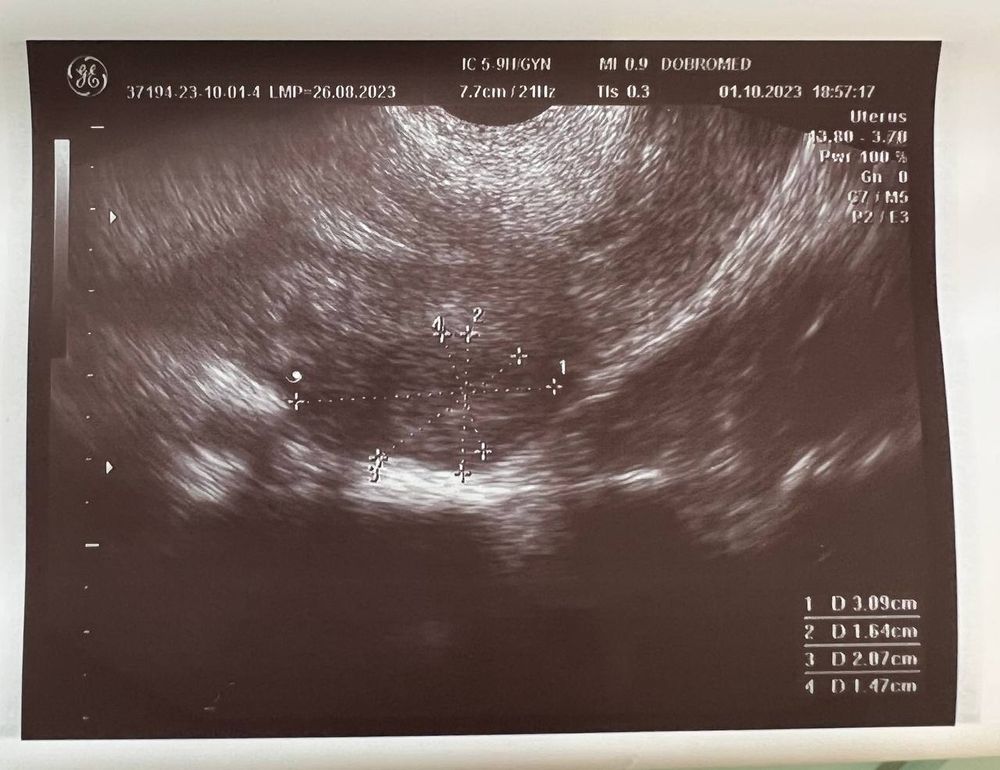

Вчера (1 октября) сходила на УЗИ, беременность подтвердили, маточная.

Размер плодного яйца 4 мм.

Но не видно желтое тело, и мутное содержимое плодного яйца (как она сказала). Меня напугала очень узистка... мол, может быть замершая беременность.

Если есть специалисты тут - пожалуйста, посмотрите снимок

Нормально всё у вас. Желтое тело есть, просто большое (киста), это часто бывает у беременных